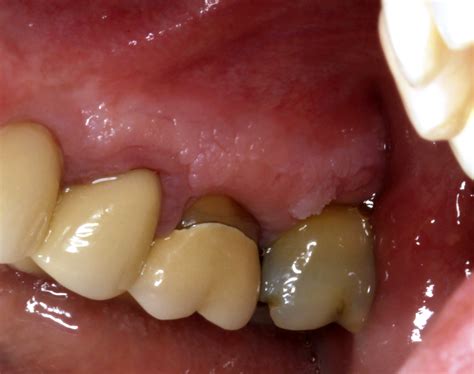

Leukoplakia on the lips is a condition characterized by the appearance of thick, white patches on the lips. These patches are typically painless but can be a cause for concern due to their potential to develop into cancer. Understanding the causes, symptoms, and treatment options for leukoplakia on the lips is crucial for early detection and effective management.

Leukoplakia on the lips refers to the development of white patches or plaques that cannot be scraped off. These patches are usually found on the inner surfaces of the lips and can vary in size and shape. The condition is more common in individuals who smoke or use tobacco products, as well as those who consume excessive amounts of alcohol.

Leukoplakia on the lips often presents with the following symptoms:

• Thick, white patches or plaques on the lips that cannot be scraped off.

• Patches that may be slightly raised or have a rough texture.

• Patches that can be painless or cause discomfort, especially if they become inflamed or infected.

• In some cases, the patches may develop into ulcers or sores.